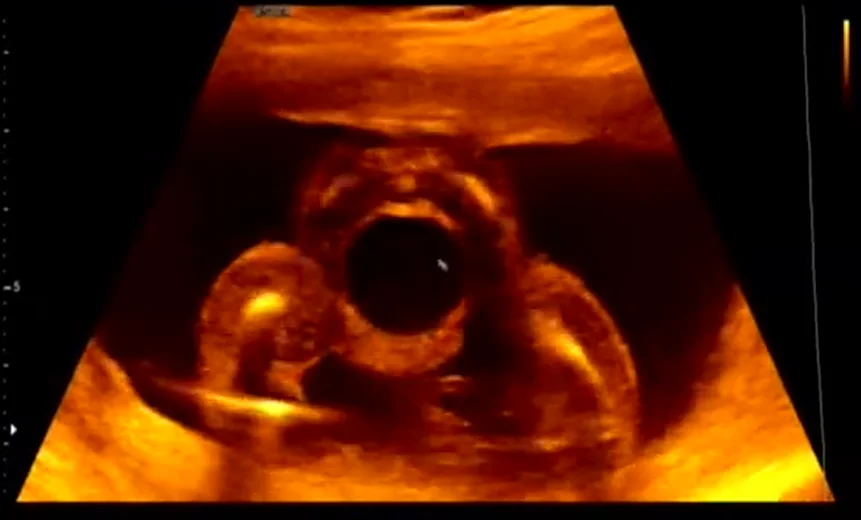

• Bàng quang to (Megacystis) và tắc nghẽn đường tiết niệu dưới (Lower urinary tract obstruction)

• Van niệu đạo sau ở thai nhi (Posterior Urethral Valves - PUV)

• Hội chứng bụng hình quả mận ở thai (Prune-Belly Syndrome)